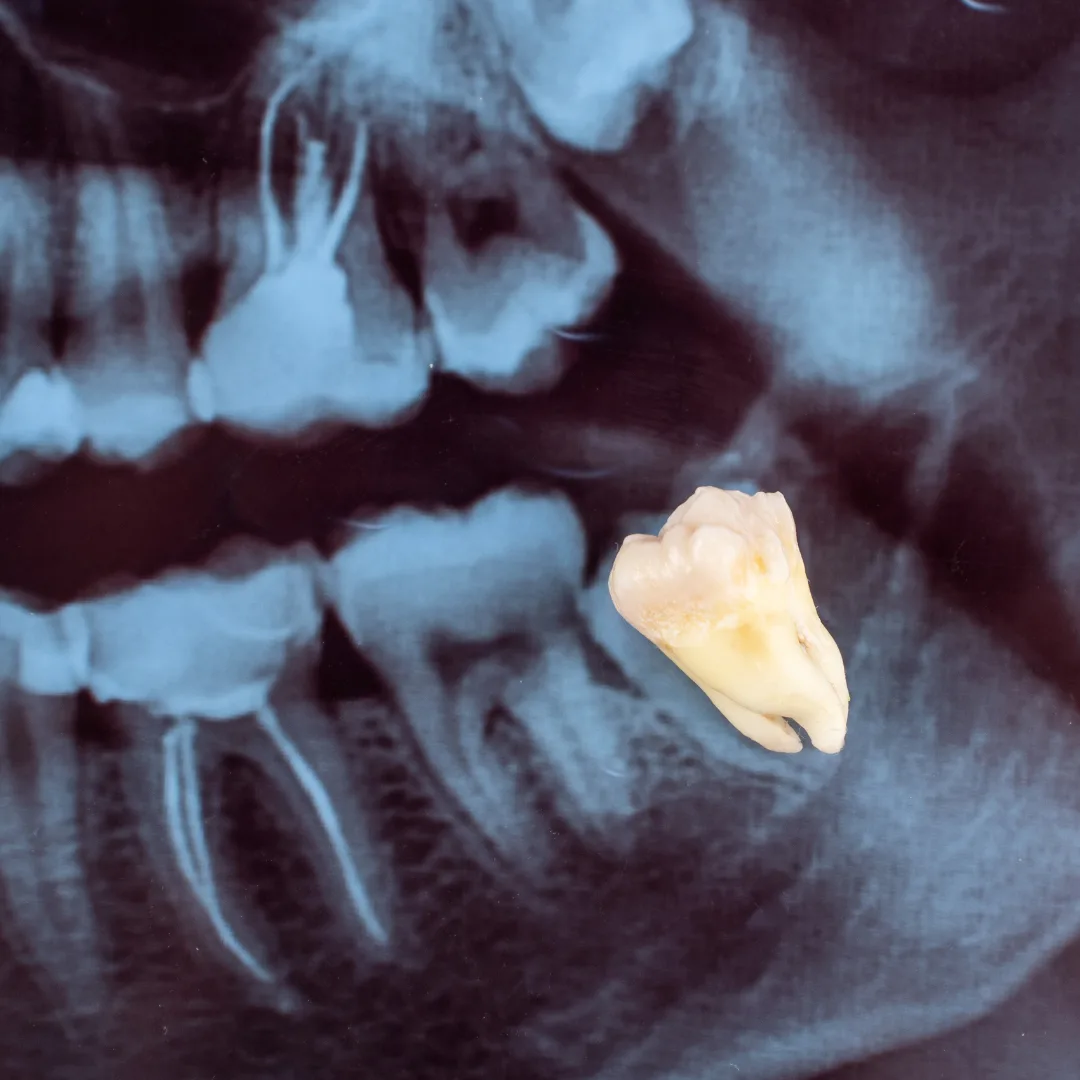

- Impacted Wisdom Teeth: Third molars are stuck under gum or bone, causing pain, infection, or crowding.

For impacted teeth or teeth with curved roots, we may perform a surgical extraction, which requires a small incision, removal of bone, and sometimes division of the tooth into sections for easier removal. Surgical extractions may require a few stitches.

A simple extraction is for teeth that are visible and loose enough to be removed with forceps. A surgical extraction is for teeth that are impacted, broken below the gum line, or have curved roots. Both are performed gently; surgical extractions may require a small incision and stitches.